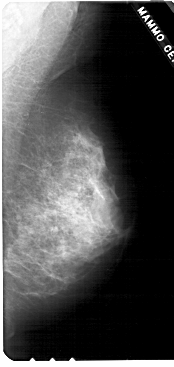

A_1790_1.LEFT_CC

LEFT_CC LINES 5281 PIXELS_PER_LINE 2281 BITS_PER_PIXEL 12 RESOLUTION 43.5 OVERLAY